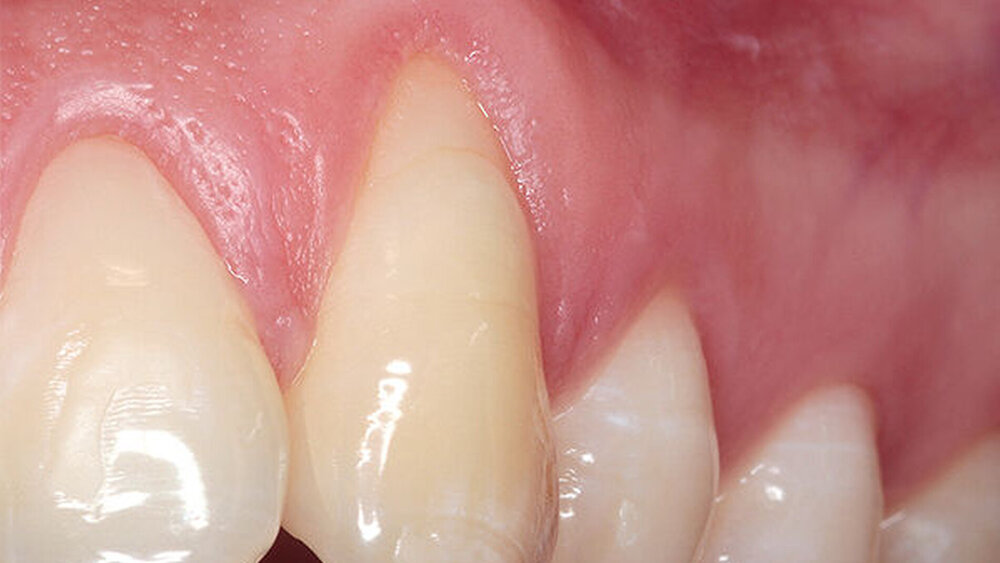

Der Erhalt oder die Gestaltung der den Zahn bzw. das Implantat umgebenden Gewebe ist notwendig als Grundlage für ein gesundes und nachhaltig stabiles, funktionelles und ästhetisches stomatognathes System. Das bedeutet: In unserem Konzept wollen wir möglichst zahnumgebende Gewebe gesund und stabil erhalten. Auf eine einfache Formel gebracht, sind es mindestens zwei Millimeter keratinisierte und angewachsene, unverschiebliche – gesunde – Gingiva um Zähne und Implantate.

An erster Stelle steht die antiinfektiöse Therapie. Strukturell-funktionelle und/oder ästhetische Gewebedefizite an Zähnen können mit mukogingival-chirurgischen Techniken stabilisiert werden (Abb. 2). Die systematische Dokumentation des Gingivaverlaufs mit einem Scan könnte die Progredienz der Rezessionen, aber auch die Regeneration infolge des Creeping Attachment nach einem chirurgischen Eingriff deutlich machen und die Vorhersagbarkeit verschiedener Methoden gegenüberstellen. Die bildgestützte Darstellung der Situation könnten zur Patienteninformation und in der Folge auch zur Motivation genutzt werden, um eine rechtzeitige Behandlung durchzuführen (Abb. 3, Abb. 4 + 5) .

Zusätzlich kann das Emergenzprofil bereits intraoperativ in der Implantationssitzung gesteuert werden. Der Scan der ausgeheilten Situation vor der prothetischen Versorgung eröffnet die Möglichkeit, durch Einmatchen des Implantats in den Datensatz die subgingivale Situation zu simulieren ohne die Darstellung einer „Präparationsgrenze“ durch das Einlegen von Fäden. Diese Manipulationen sind traumatisch und zerstören die sensible hemidesmosomale Anhaftung der Gingiva- und Bindegewebsfasern an der Implantatoberfläche. Der digitale Abdruck wird die konventionelle Abformung in der modernen Zahnarztpraxis aufgrund seiner überlegenen Performance ersetzen. Den parodontologischen und minimalinvasiven Prinzipien folgend, ist die digitale Abformung von Zähnen auch in der ästhetisch sensiblen Zone angesichts der geringeren Traumatisierung der parodontalen Gewebe, der überragenden Präzision und der daraus folgenden Randpassung der Versorgung ein logischer und richtiger Weg in die Zukunft der zahnärztlichen Praxis (Abb. 10 – 14).